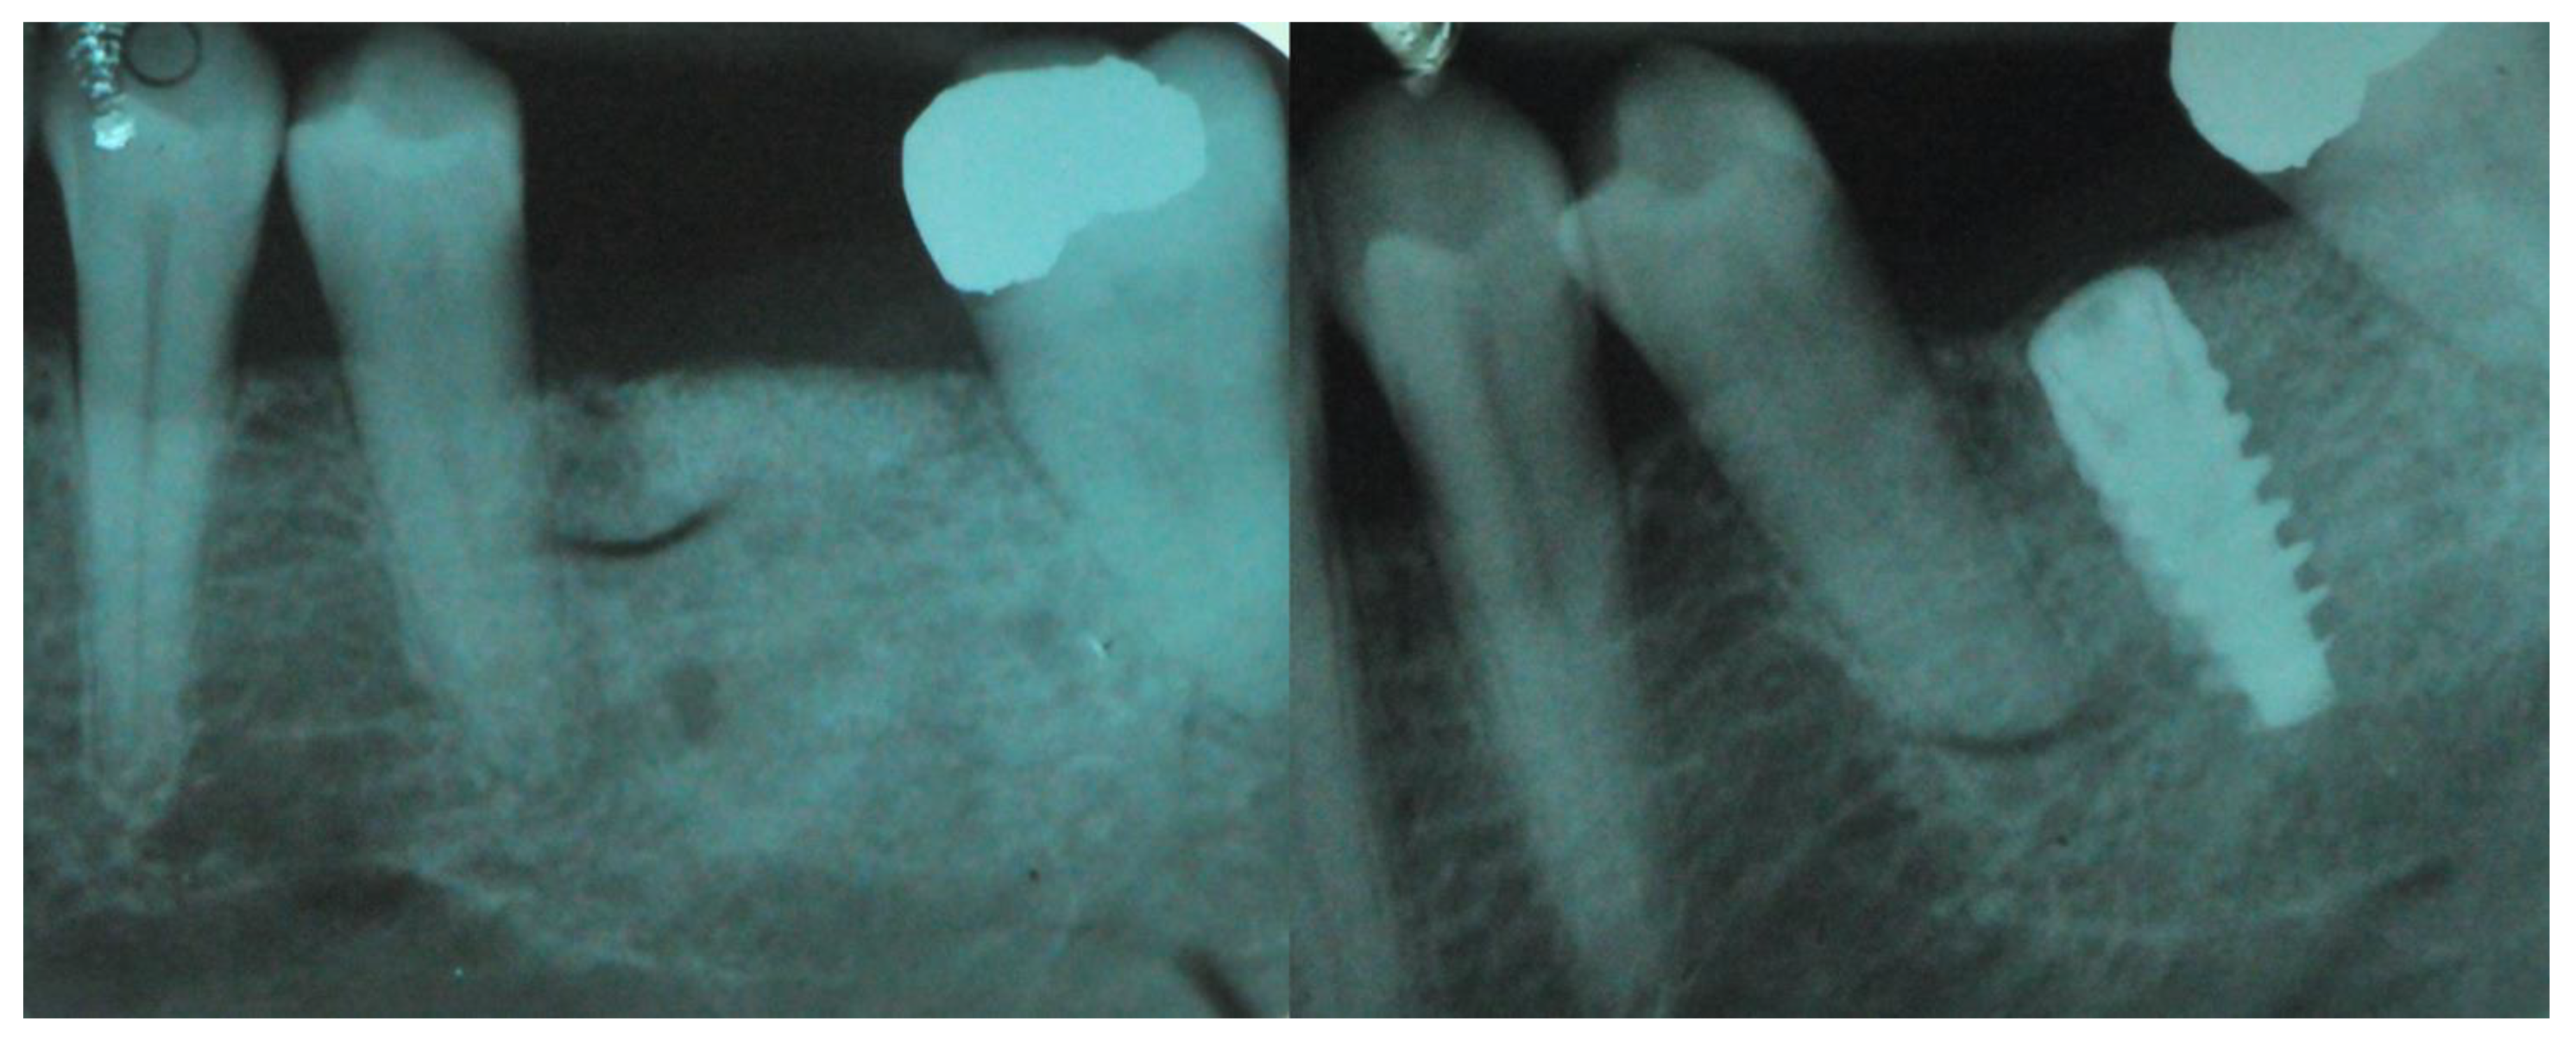

Figure 5.

Intra oral radiograph before and after implant placement. Left: intra-oral X-ray after grid removal and healing occurred. Right: fixture installation.